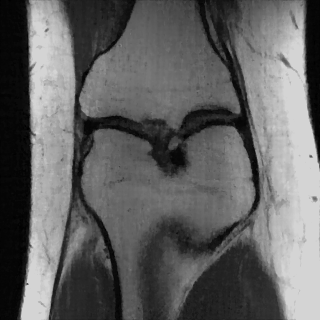

This article presents a novel undersampled magnetic resonance imaging (MRI) technique that leverages the concept of Neural Radiance Field (NeRF). With radial undersampling, the corresponding imaging problem can be reformulated into an image modeling task from sparse-view rendered data; therefore, a high dimensional MR image is obtainable from undersampled $k$-space data by taking advantage of implicit neural representation. A multi-layer perceptron, which is designed to output an image intensity from a spatial coordinate, learns the MR physics-driven rendering relation between given measurement data and desired image. Effective undersampling strategies for high-quality neural representation are investigated. The proposed method serves two benefits: (i) The learning is based fully on single undersampled $k$-space data, not a bunch of measured data and target image sets. It can be used potentially for diagnostic MR imaging, such as fetal MRI, where data acquisition is relatively rare or limited against diversity of clinical images while undersampled reconstruction is highly demanded. (ii) A reconstructed MR image is a scan-specific representation highly adaptive to the given $k$-space measurement. Numerous experiments validate the feasibility and capability of the proposed approach.